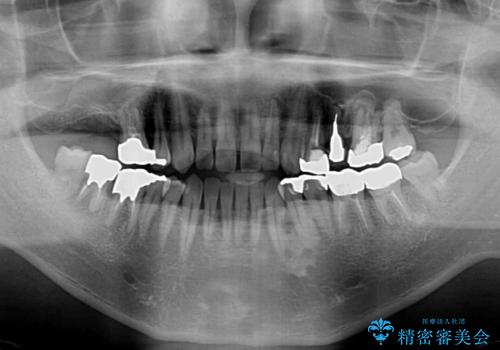

来院当初は、奥歯の銀歯が問題で咬み合わせが悪いと思っていらっしゃいましたが、前歯の反対咬合を改善することが最優先とご説明し、矯正治療を行うこととしました。

奥歯には抜歯が必要な歯があったため、事前に抜歯を行い、その後ワイヤー装置にて治療を開始しました。

前歯の反対咬合が改善する過程では、奥歯が咬みにくくなるため、食事では辛い思いをされていたようです。

矯正治療後は安定した咬み合わせとなり、顎の違和感がなくなったとのことでした。

今後はむし歯や銀歯を治療していく予定です。